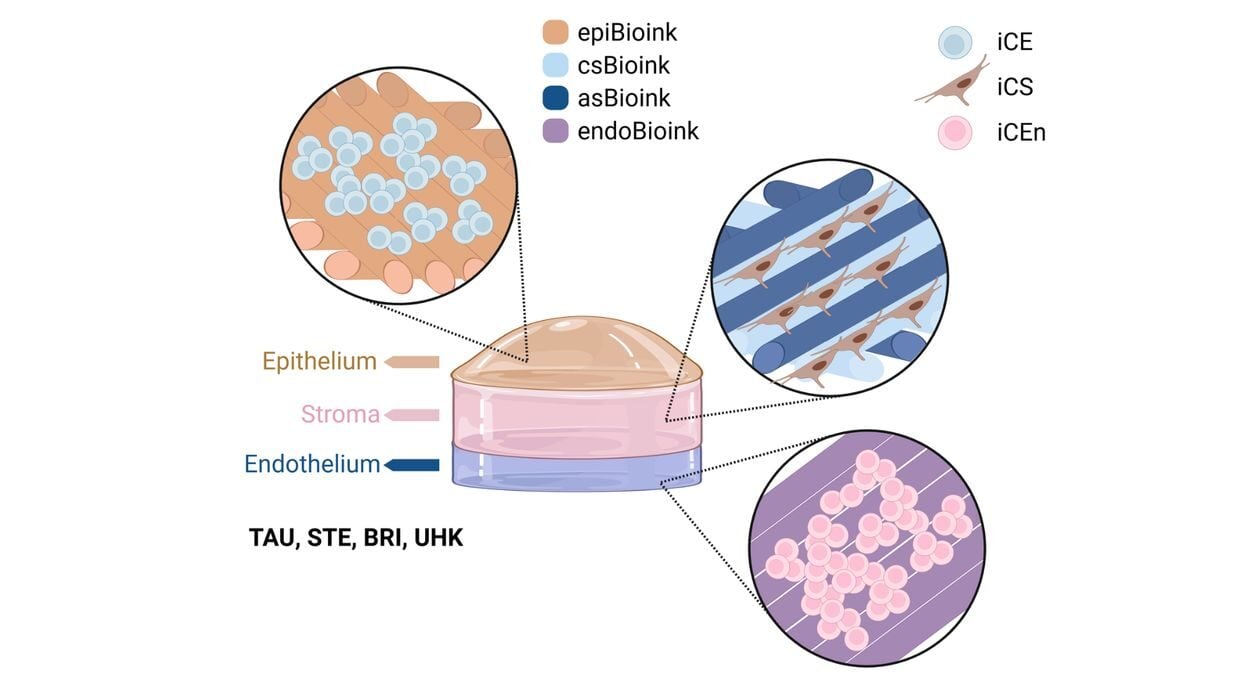

KeratOprinter Project Aims to 3D Print Corneas to Address Global Donor Shortage

The KeratOPrinter hopes to solve corneal blindness with new technology.